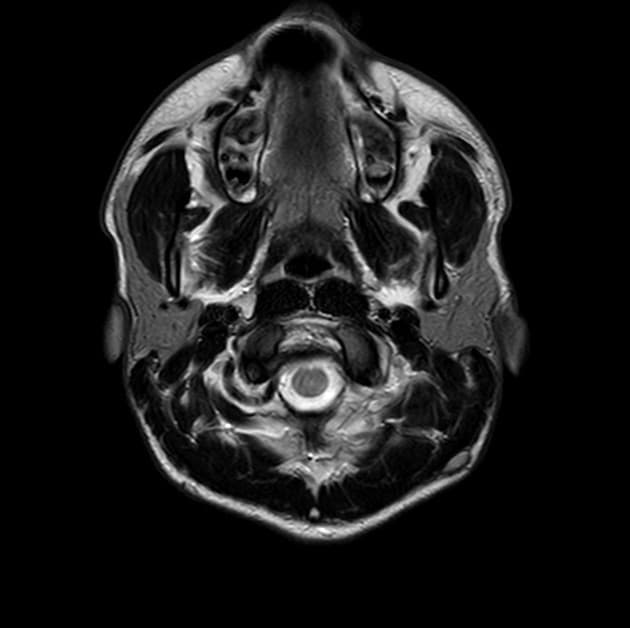

Axial FLAIR

- Vùng tín hiệu bất thường dạng không đều trên hình ảnh cộng hưởng từ trọng T2 và FLAIR, kèm dày lớp dưới vỏ và rãnh não nông ở thuỳ đỉnh – thái dương phải, lan tới vùng quanh tam giác của não thất bên cùng bên

- Lượng chất xám dưới biểu mô tăng bất thường dọc theo thành bên của sừng thái dương và vùng quanh tam giác não thất bên phải, gây hình ảnh uốn lượn thành não thất

- U nang màng nhện lớn ở thuỳ thái dương trước trái

- Thể chai (corpus callosum) bình thường

- Không có bằng chứng của hạn chế khuếch tán (restricted diffusion) ở bất kỳ vùng nào của não